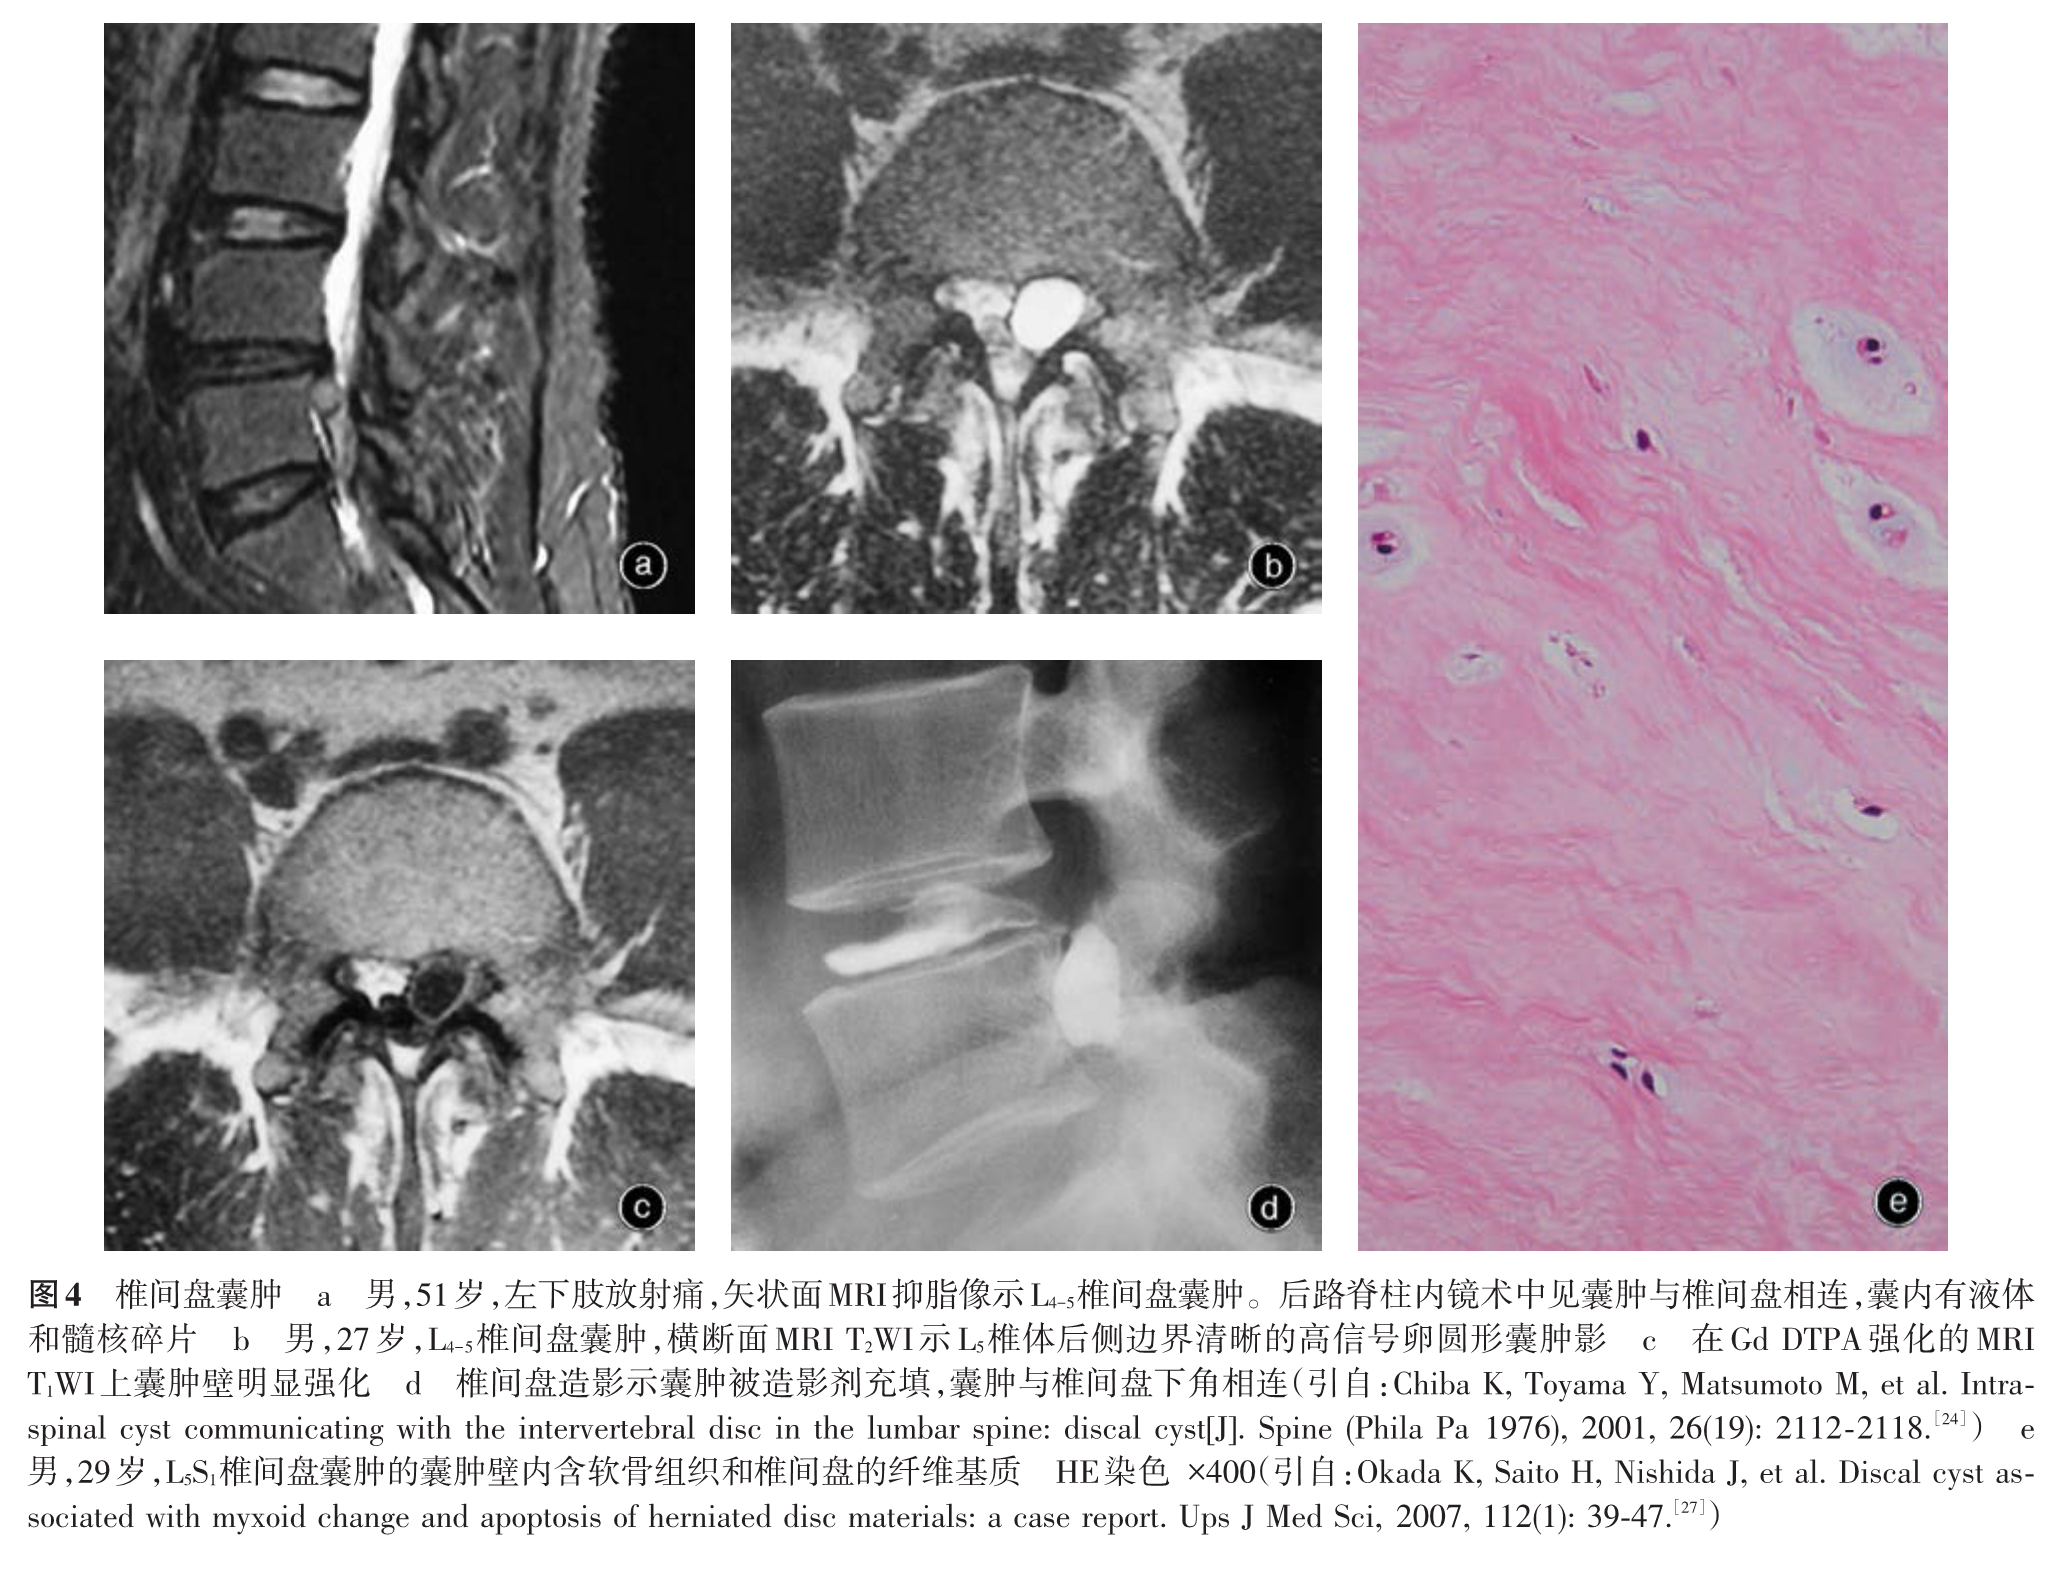

我们在临床实践中发现腰椎间盘突出症在大体病理、免疫学等方面存在较大差异,病变周围组织也有不同的病理改变,存在不同的发病机制,其治疗措施包括手术方法因不同的病理变化而有所差异。基于以上认识,我们在以往分类方法的基础上提出一种新的腰椎间盘突出症病理学分型,分为损伤疝出型、退变突出型、椎体后缘骨软骨病伴椎间盘突出和椎间盘囊肿四型[5-11],并建议根据不同的病理类型进行临床评估,包括手术方法的选择。